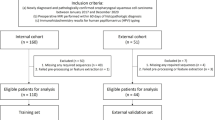

Four hundred ninety-five patients in the collection of data from The Cancer Imaging Archive (TCIA) [42] were included in the study. The study only examined 238 individuals’ contrast-enhanced CT scans, 204 of whom were HPV positive and had been given an OPC diagnosis. The gross primary tumor volume (GTVp) (see Fig. 1), which is divided by experts, is taken into account in radiomic research [35].

The 1142 features were subject to Z-score normalization. Twenty percent of the data was designated for testing, while the remaining 80% was designated for training. There was an uneven distribution of HPV classes between the training set and the test set. The test set contained 48 instances (43 HPV positive, 5 HPV negative), while the training set contained 190 cases (161 HPV positive, 29 HPV negative).

Since the number of cases with HPV status was imbalanced, the random over-sampling (ROSE) [49] resampling method was utilized. Only the training set was subjected to a resampling technique, and 161 samples for each positive and negative HPV class were obtained (see Fig. 3).